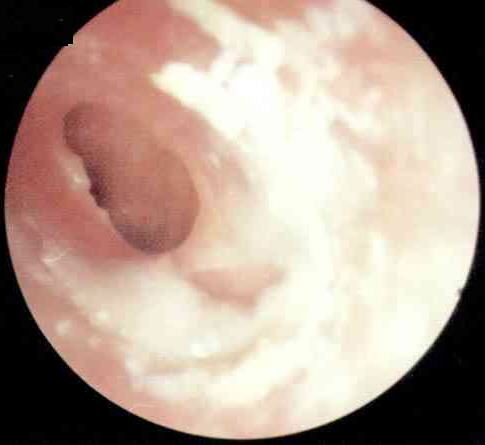

卡他性中耳炎病理图

当咽鼓管功能障碍时,外界控制不能进入中耳,中耳内原有的气体逐渐被粘膜吸收,腔内形成相对负压,引起中耳粘膜静脉扩张、淤血、血管壁通透性增强,鼓室内出现漏出液。如负压不能得到除掉,中耳粘膜可发生一系列病理变化,主要表现为上皮增厚,上皮细胞化生,鼓室前部低矮的假复层柱状上皮变为增厚的纤毛上皮,鼓室后部的单层扁平上皮变为假复层柱状上皮,杯状细胞增多;分泌亢进,上皮下病理性腺体组织形成,固有层血管周围出现以淋巴细胞及浆细胞为主的圆形细胞浸润。疾病恢复期,腺体逐渐退化,分泌物减少,粘膜渐恢复正常。